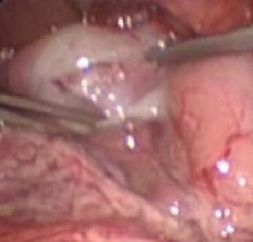

Laparoscopic knife pyloric incision

From the collection of Dr Jeffrey S. Upperman; used with permission